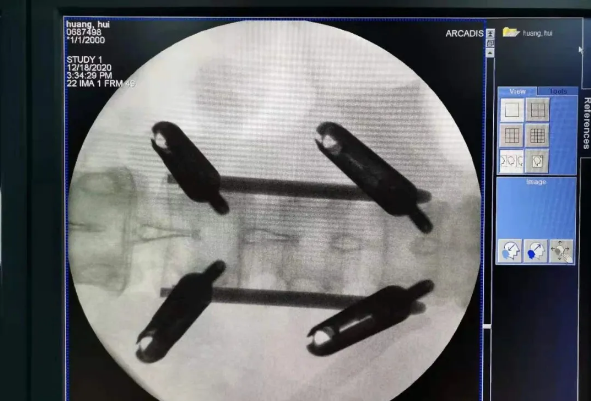

天玑?骨科手术机械人系统由机械臂主机、光学跟踪系统、主控台车组成,,,,,“透视眼”、“稳固手”是它的厉害之处,,,,,因此一举解决了骨科手术有三浩劫题:视野差、精准难、不稳固。。。。。。

? 光学跟踪系统就像是天玑?骨科手术机械人的“透视眼”,,,,,不但透视洞察着肌肉骨骼的每一个深处,,,,,还实时监控每一个手术环节;;;;;

? 机械臂就是天玑?骨科手术机械人的“稳固手”,,,,,运动无邪、操作稳固,,,,,能抵达亚毫米的精度;;;;;

? 主控电脑系统就即是天玑?骨科手术机械人的大脑,,,,,智能转达着医生的想法给以上两个装备,,,,,资助医生举行“路径妄想”,,,,,术中还能跟踪患者术中的移动,,,,,机械人手臂位置自动赔偿,,,,,包管手术路径与妄想路径一致。。。。。。